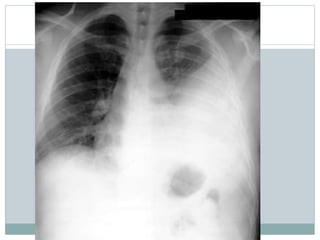

Avalie o raio x , descreve bem a

patologia cardiaca,

Conclusão?

Tecnica:

rotada, pouco penetrado,

revelação boa, tirado deitado e inclinado

Patologia:

• Cardiomegalia grave,

• com atrio esquerdo muito prominente

• Ventriculo esquerdo e atrio direito também

dilatados

• Trama vascular aumentada

Conclusão:

(11 anos, clinicamente IC que agravou ha uma semana)

Raio X tipico de insuficiencia mitral (provavelmente devido FR) com IC

descompensada

• NB como a penetracao é muito diminuida corremos risco de “ ver” lesões

pulmonares amais, neste caso não ha infiltrado pulmonar, apenas congestão

pulmonar!